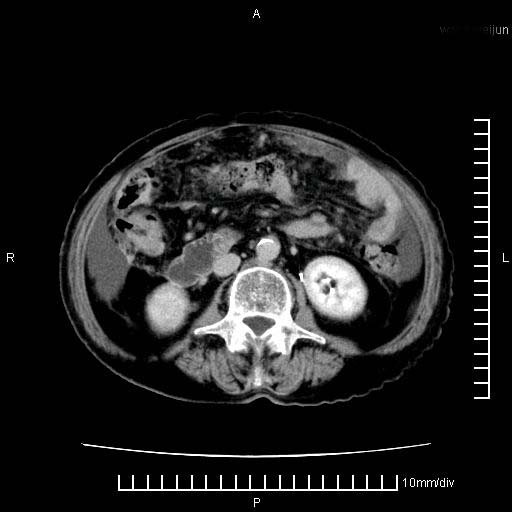

上腹疼痛月余,外院核磁诊断胰腺癌。现临床示右下腹可明显触及包块,可片子上怎么没有看到?

1.胰腺颈体部癌。

2。腹腔积液。

胰腺体部癌累及周围器官,腹膜、粘连

1。胰腺ca伴腹膜腔转移

2。肝左叶低密度灶,考虑转移可能

胰腺结构模糊,胰尾部见囊性包块,周围脂肪密度增高,左肾前筋膜增厚,胸水、腹水。不符合胰腺ca伴腹膜腔转移。考虑胰腺炎伴假性囊肿形成、胸腹腔积液。

1、考虑胰腺癌伴腹膜腔转移,胸腹水。

1)考虑胰腺癌并胰腺假性囊肿形成。2)肝内低密度灶,不排除转移。3)右肾盂积水。4)腹水。5)右侧胸腔积液并右肺下叶部分膨胀不全。

考虑胰腺ca伴腹膜腔转移、肝左叶转移、右肾积水。右胸腔积液。